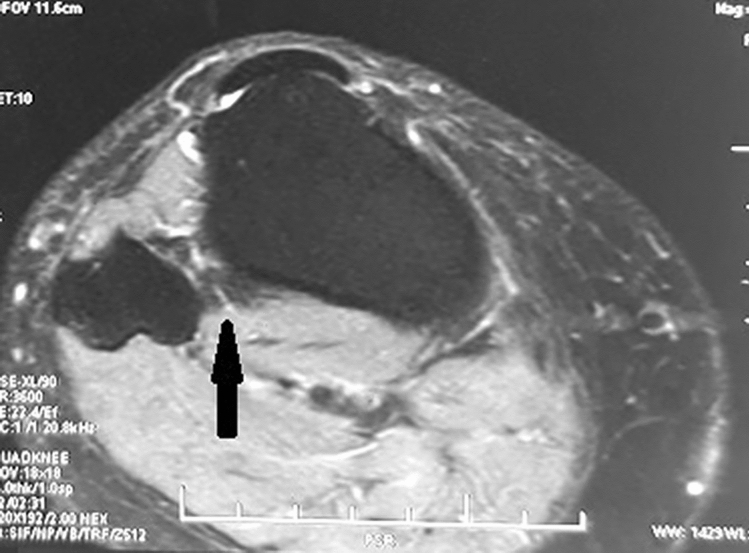

Fig. 1.

MRI STIR images showing hypointense signal intensity at PTFJ depicting injury (solid arrow)